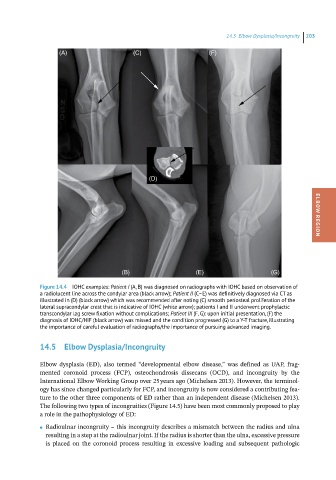

Figure 14.4 IOHC examples: Patient I (A, B) was diagnosed on radiographs with IOHC based on observation of

a radiolucent line across the condylar area (black arrow); Patient II (C–E) was definitively diagnosed via CT as

illustrated in (D) (black arrow) which was recommended after noting (C) smooth periosteal proliferation of the

lateral supracondylar crest that is indicative of IOHC (white arrow); patients I and II underwent prophylactic

transcondylar lag screw fixation without complications; Patient III (F, G): upon initial presentation, (F) the

diagnosis of IOHC/HIF (black arrow) was missed and the condition progressed (G) to a Y-T fracture, illustrating

the importance of careful evaluation of radiographs/the importance of pursuing advanced imaging.